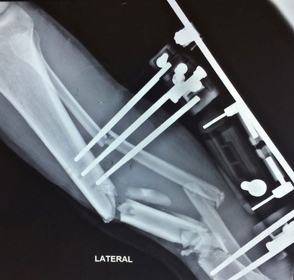

De acuerdo a publicaciones que realiza desde hace dos semanas Listín Diario el mercado de comercialización y colocación de implantes ortopédicos, como prótesis de rodilla, cadera y hombros, así como materiales de osteosíntesis, como clavos, placas, tornillos, entre otros, que se utilizan en las cirugías del área de la traumatología, ha estado funcionando en el país por más de 40 años sin una eficaz regulación.

De ahí que, de acuerdo a especialistas en el área, en los últimos años haya surgido una gran cantidad de empresas suplidoras de esos materiales, muchos de los cuales no cuentan con la debida aprobación de la Administración de Alimentos y Fármacos de Estados Unidos (FDA), ni de permisos sanitarios locales. Debido a esa realidad, la seguridad del paciente queda en manos de la exclusiva discrecionalidad y conciencia del médico o del centro de salud donde se ofrece el servicio, agravado, por el hecho, de acuerdo a los denunciantes, de que luego de que se lograra incluir esos materiales en la cobertura del SDSS, las aseguradoras se involucran y con frecuencia devuelven los expedientes médicos y ponen condiciones de elegir determinada marca para aprobar el material que se utilizará en la cirugía de su afiliado.